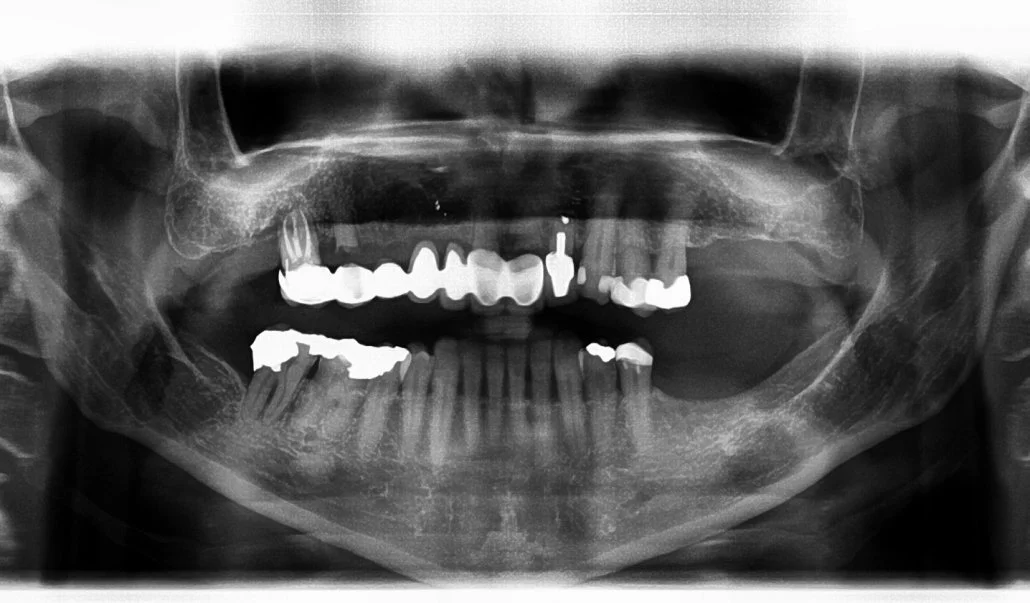

Occlusal Reorganisation

Marijka is a delightful lady with a very marked skeletal Class 3 presentation. She was referred to The Implant Centre by her dentist as her 7-unit upper bridge was clearly failing. This bridge had been fitted 24 years before, but the supporting teeth had undergone both severe decay as well as periodontal bone loss.